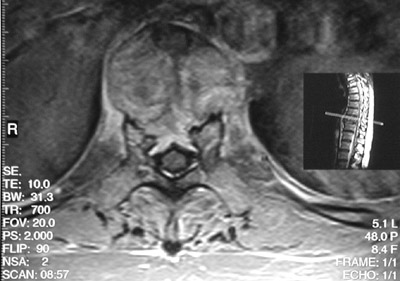

This MRI scan in axial view demonstrates bony destruction of the T3 vertebral body in a patient with metastatic renal cell carcinoma.